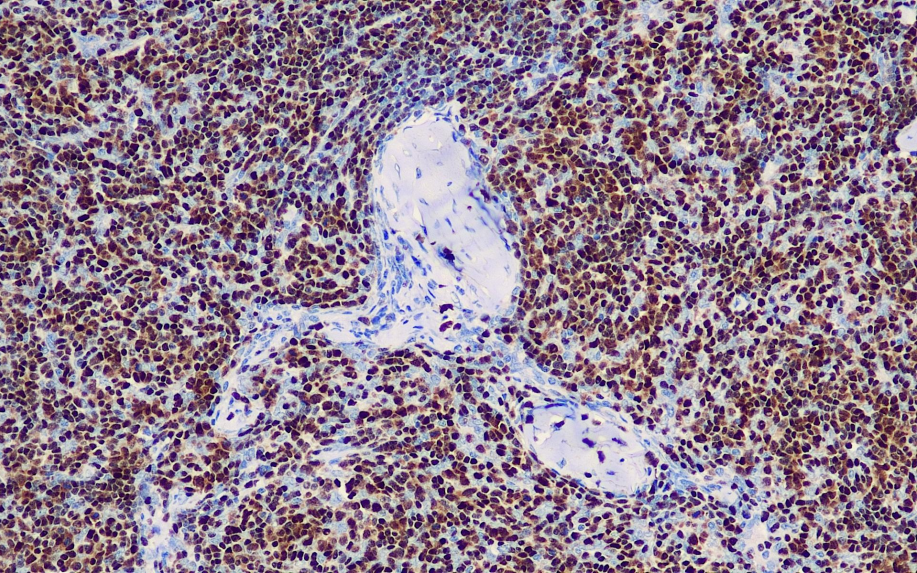

Positive control: Thymus

Terminal deoxynucleotidyl transferase (TdT) is a DNA polymerase that can catalyze the insertion of free deoxynucleotides into the 3'-OH end of a DNA strand without the need for a template. TdT is considered a relatively specific reference for acute lymphoblastic lymphoma/leukemia.

TdT antibody reagents can specifically bind to TdT molecular antigens. Immunohistochemistry kits containing TdT antibody reagents are suitable for the precise diagnosis of acute lymphoblastic lymphoma and leukemia.